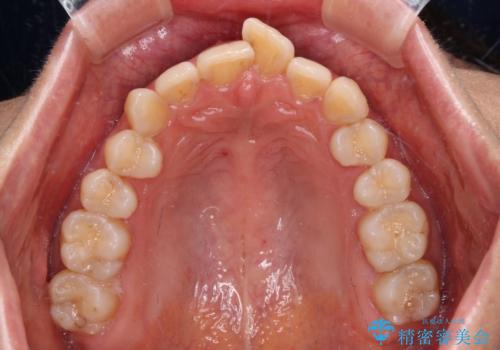

- 上下前歯のデコボコを気にして来院された患者様です。

叢生は軽度で、ワイヤー矯正でもマウスピース矯正でも対応可能な歯列でした。

僅か1年間できれいに歯列を整えることができ、患者様には大変満足していただきました。